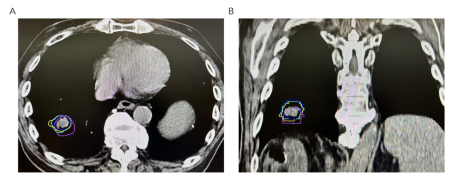

肺部与其他部位肿瘤存在的最重要的不同在于,肺部是一个不断运动的器官,随着我们的呼吸,肺部会不断地膨胀和收缩。这就意味着,肺部的肿瘤也会随之移动。如果不能准确地"看见"肿瘤的位置,很容易造成放疗时"打偏",既达不到治疗效果,还可能伤及周围的正常组织。所以肺部肿瘤放疗定位时,经常需要进行4D-CT扫描,它不仅能提供静态的图像,还能捕捉肿瘤随呼吸运动的轨迹。通过4D-CT,医生可以了解肿瘤在不同呼吸阶段的位置变化,从而根据患者独特的肺肿瘤呼吸运动情况,有针对性地制定个体化的放疗计划。如图1所示:不同颜色的曲线代表呼吸周期中不同时相下肺部肿瘤位置,从该图可以看出,呼吸运动过程中肺部肿瘤有较大的位置变化。制定放疗计划时不同呼吸时相肿瘤运动的范围要全部包括在放疗的照射范围内,这样就可以保证不管是吸气末还是呼吸末,肿瘤始终逃不出放射线的五指山。这个过程同样需要患者的配合,并且配合的程度直接决定了肿瘤放疗的效果以及正常肺损伤的损伤情况。试想一下,如果4D-CT扫描过程中,患者始终保持深呼吸,那肿瘤的移动范围必然增加,进一步的放疗的照射范围随之增加,这样正常组织出现损伤的概率必然增加。最严重的情况,定位时患者小幅度呼吸,放疗时因为紧张等变成了大口呼吸,那肿瘤将脱离我们设定好的照射范围,这样放疗后肿瘤很快就会进展。那最理想的状态是,放疗定位时稍微早到一会,熟悉环境和流程,不要紧张,定位开始后要小幅度的浅呼吸,这样肺肿瘤的运动幅度就相应减少。最重要的,放疗时要保持和定位时一致的浅呼吸,切记不可转为深呼吸,以免肿瘤逃出我们根据浅呼吸状态下制定的放疗照射范围。

图1:不同呼吸时相下肿瘤位置变化。